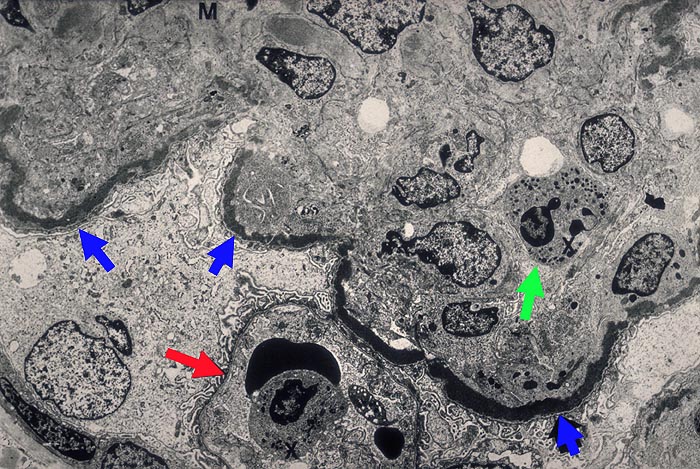

Eine der ► Schlingen weist keine osmiophilen Depots auf. In der benachbarten Schlinge massive, ► bandförmige Depots. In den Schlingenlumina findet man ► neutrophile Granulozyten, daneben auch Monozyten. Im Mesangium besteht eine deutliche Sklerose, begleitet von einzelnen osmiophilen Depots.

Im EM: intramembranöse stark osmiophile bandförmige Depots auch in der Bowman'Kapselbasalmembran, Arteriolen und tubulären Basalmembranen. DD: Leichtketten Nephropathie.